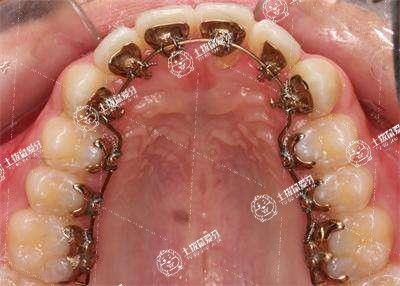

矯正牙齒弓絲末端扎嘴 矯正牙齒弓絲一直斷了咋辦

矯正牙齒弓絲末端扎嘴

弓絲末端扎嘴,可通過(guò)使用正畸保護(hù)蠟、或及時(shí)就醫(yī)調(diào)整弓絲末端方向等方法進(jìn)行改善,如弓絲末端扎嘴導(dǎo)致口腔黏膜破損、潰瘍,可在醫(yī)生指導(dǎo)下使用口腔潰瘍散、西瓜霜等藥物促進(jìn)愈合。

如出現(xiàn)弓絲末端扎嘴的情況,可能是由于患者頰部黏膜肥厚,可在醫(yī)生指導(dǎo)下取一段正畸保護(hù)蠟,用手捏成圓球,放在正畸矯治裝置弓絲末端扎嘴的位置上,在吃飯時(shí)取下,以免誤吸誤咽,飯后重新粘住。

也可能是由于弓絲太長(zhǎng)或末端沒(méi)有貼向牙齒表面導(dǎo)致的,可就診口腔科,在專業(yè)醫(yī)生操作下調(diào)整末端的彎曲方向,剪除過(guò)長(zhǎng)弓絲,從而緩解扎嘴的情況。

如果帶了正畸矯治器,弓絲的末端扎頰部的黏膜,可以用鉗子將弓絲的末端卷成一個(gè)小的圈,這樣末端的尖銳部分就不會(huì)直接刺激頰黏膜,造成疼痛。也可以將弓絲的末端彎向牙弓最遠(yuǎn)端的牙面遠(yuǎn)中,沿著牙面進(jìn)行分布,繞過(guò)牙面到腭側(cè)或者舌側(cè),這樣就不會(huì)扎到頰黏膜。

如果不會(huì)進(jìn)行上述的調(diào)整,也可以先在弓絲的遠(yuǎn)端和頰黏膜之間塞一個(gè)小棉球,就可以將頰黏膜和弓絲隔開(kāi),弓絲就不會(huì)扎到頰黏膜上。盡早到正規(guī)醫(yī)院的口腔科或者正畸科醫(yī)生處就診,醫(yī)生有專用的器械可以進(jìn)行調(diào)整,避免再扎頰黏膜。